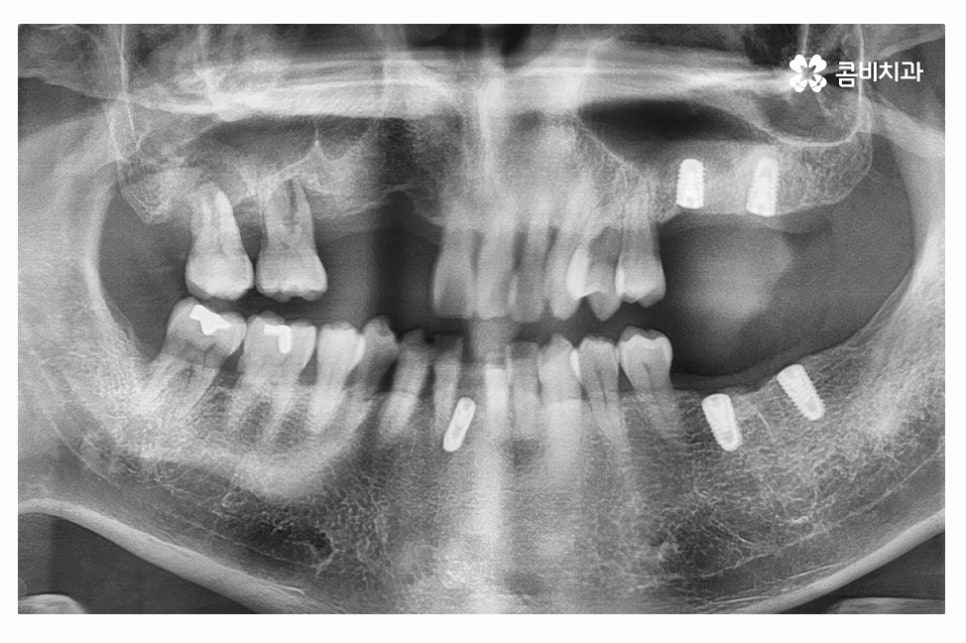

임플란트의 구성을 살펴보면 치아를 발치한 후에는 임플란트의

인공치근을 심게 되며(사진에서 좌측), 인공치근에

지대주(사진에서 우측)를 연결한 후에 지대주에 보철물을 연결하게 되며

임플란트가 단단하게 고정되기 위해서는 잇몸 뼈와

인공치근의 골 유착 과정을 건강하게 거쳐야 할 필요가 있어요.

우측 사진의 경우 힐링어버트먼트를 장착한 모습인데, 일반적으로는

1차 수술을 마치고 약 1개월 정도 후 임플란트 어버트먼트가 들어가기 전에

어버트먼트가 잘 들어갈 수 있도록 잇몸의 모양을 잡아 주기 위해 장착을 하며,

잇몸뼈가 건강하고, 식립이 잘 되었다면 1차 수술을 하면서 바로

힐링어버트먼트를 장착하는 경우도 있지만, 정석은 2차 수술 때 장착을 하는 경우라고 할 수 있어요.